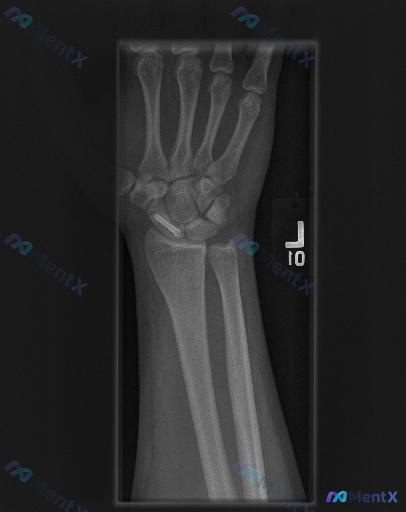

整理到一张左侧腕关节正位X光片的影像资料,背景是患者有舟骨内固定手术史。 主要影像表现: - 左侧舟骨腰部可见一枚金属螺钉内固定影,螺钉穿透舟骨长轴,位置尚可 - 舟骨形态大致连续,未见明显新鲜骨折线 - 桡骨远端、尺骨茎突及其余腕骨轮廓清晰,未见明显骨折或脱位 - 桡腕关节、下尺桡关节间隙尚可,腕...